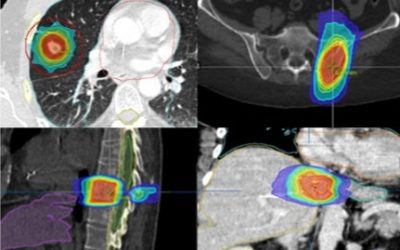

La radiocirugía craneal (SRS) y extracraneal (SBRT), parte III. Alcance

¿Hasta dónde llegan la radiocirugía craneal y extracraneal (SRS y SBRT)? Ambos tratamientos se diseñan como un “traje a medida” de las metástasis a tratar. Gracias a las pruebas de imagen como el...

La radiocirugía craneal (SRS) y extracraneal (SBRT), parte II. Indicación clínica

Mientras el tratamiento sistémico (oral o intravenoso) suele ser la base terapéutica en las pacientes con cáncer de mama metastásico, la radioterapia y de forma específica la radiocirugía craneal y...